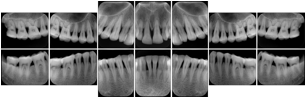

3. A dental provider wishes to capture a series of DICOM IO images for the patient’s dentition. The tooth morphology, teeth are divided into molars, premolars, canines and incisors, and a number of images for each jaw. The anatomic information was captured utilizing the triplet of schema. This standard code sequence is based on ISO 3950-2010, Dentistry - Designation system for teeth and areas of the oral cavity.

Every IO image should have anatomic information either through the primary or modifier sequence.

In most standard cases, images are oriented in structured layouts. These structured displays are useful to be shared between providers for reference purposes.

Table OO.1.1-1 shows structured display standard templates, where Viewset ID is based on the Japanese Society for Oral and Maxillofacial Radiology (JSOMR) classification provided by JIRA (Japan Medical Imaging and Radiological Systems Industries Association, www.jira-net.or.jp). Expected or typical teeth to be imaged location, region and designation codes are based on ISO 3950-2010, Dentistry - Designation system for teeth and areas of the oral cavity. For all the hanging protocols listed in OO.1.1-1, the value to use for Hanging Protocol Creator (0072,0008) is "JSOMR" and the value to use for Hanging Protocol Name (0072,0002) does not include "JSOMR" (e.g., "DL-S001A", not "JSOMR DL-S001A").